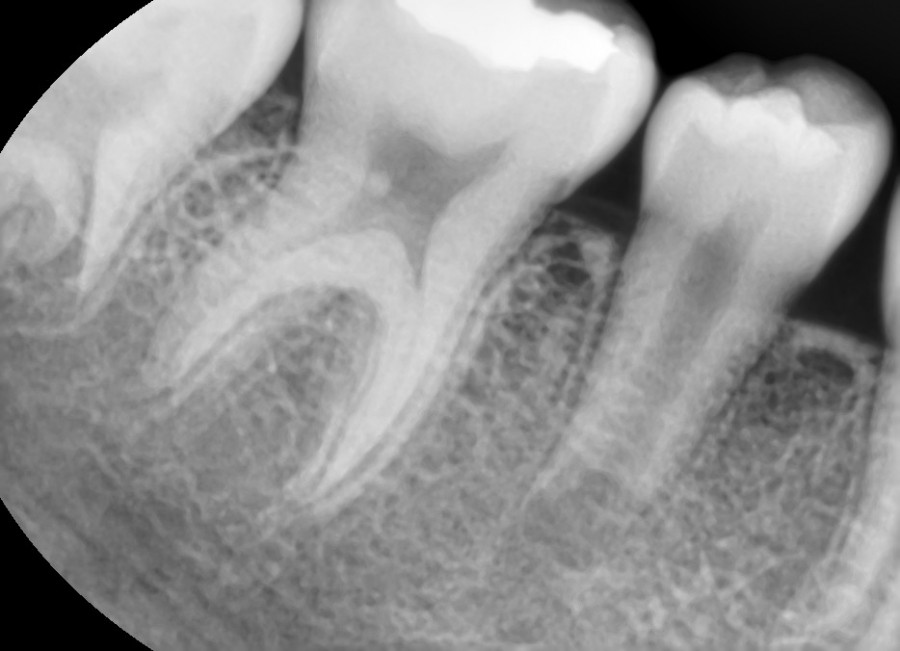

치수(신경)이 괴사되어 염증이 심한 상태로 내원한 14세 여환이었습니다. 뿌리도 다 성장하지 않은 상태였지만 MTA 신경치료를 통해 정상적인 길이로 뿌리가 성장하였고

온전히 기능하는 상태로 유지되고 있는 것을 보니 매우 다행이었습니다.